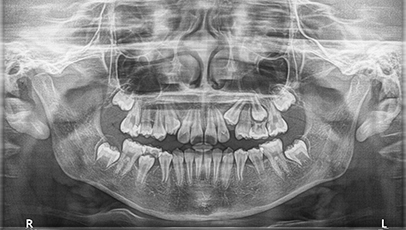

Before & After

아래 양쪽 끝 어금니가

적절한 교정치료후 똑바로 일어섰습니다